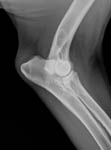

Gesundheitsstatus vom 26.11.2018 Die Röntgenbilder zeigen keinen Hinweis auf HD oder ED bei Lena vom Gehrensee. Die veterinärmedizinischen Untersuchungen von Jana auf HD, ED u. DCM und die Zuchtzulassungsprüfung wurden erfolgreich bestanden.

Die Gelenke sind HD und ED - frei, das Herz ohne Befund. Vor dem Hintergrund, dass seit 5 Generationen alle Zuchthündinnen bis ins hohe